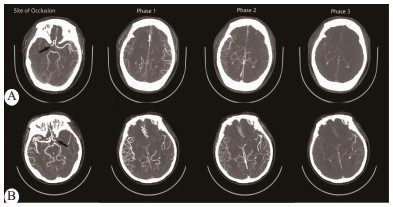

1.3.2 脑侧支循环评估根据Menon等[2]提出的Alberta Stroke Program Early CT Score (ASPECTS)侧支循环六点量表,按头颅mCTA显示的患侧MCA供血区软脑膜吻合支代偿速度及充盈数量,认为ASPECTS侧支循环评分>3分为侧支循环良好,≤3分为侧支循环不良(图 1)。侧支循环评估由工作多年的三位放射科医师采用盲法分别对研究对象的mCTA进行,若有争议以多数意见为准。据此分为侧支良好组和侧支不良组,分别有31例和18例。

| A:55岁女性,NIHSS 11分,mCTA显示RMCA闭塞,ASPECTS侧支循环得分为4分,表明侧支循环良好;B:51岁女性,NIHSS 14分,mCTA显示LMCA闭塞,ASPECTS侧支循环得分为2分,表明侧支循环不良 图 1 采用ASPECTS侧支循环六点量表评分法对患者进行侧支水平评估 Fig 1 Assessment of collateral levels in patients using the ASPECTS collateral circulation six-point scale |